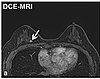

| Dynamic contrast enhanced | DCE | Measures changes over time in the shortening of the spin–lattice relaxation (T1) induced by a gadolinium contrast bolus.[76] | Faster Gd contrast uptake along with other features is suggestive of malignancy (pictured).[77] |

| |